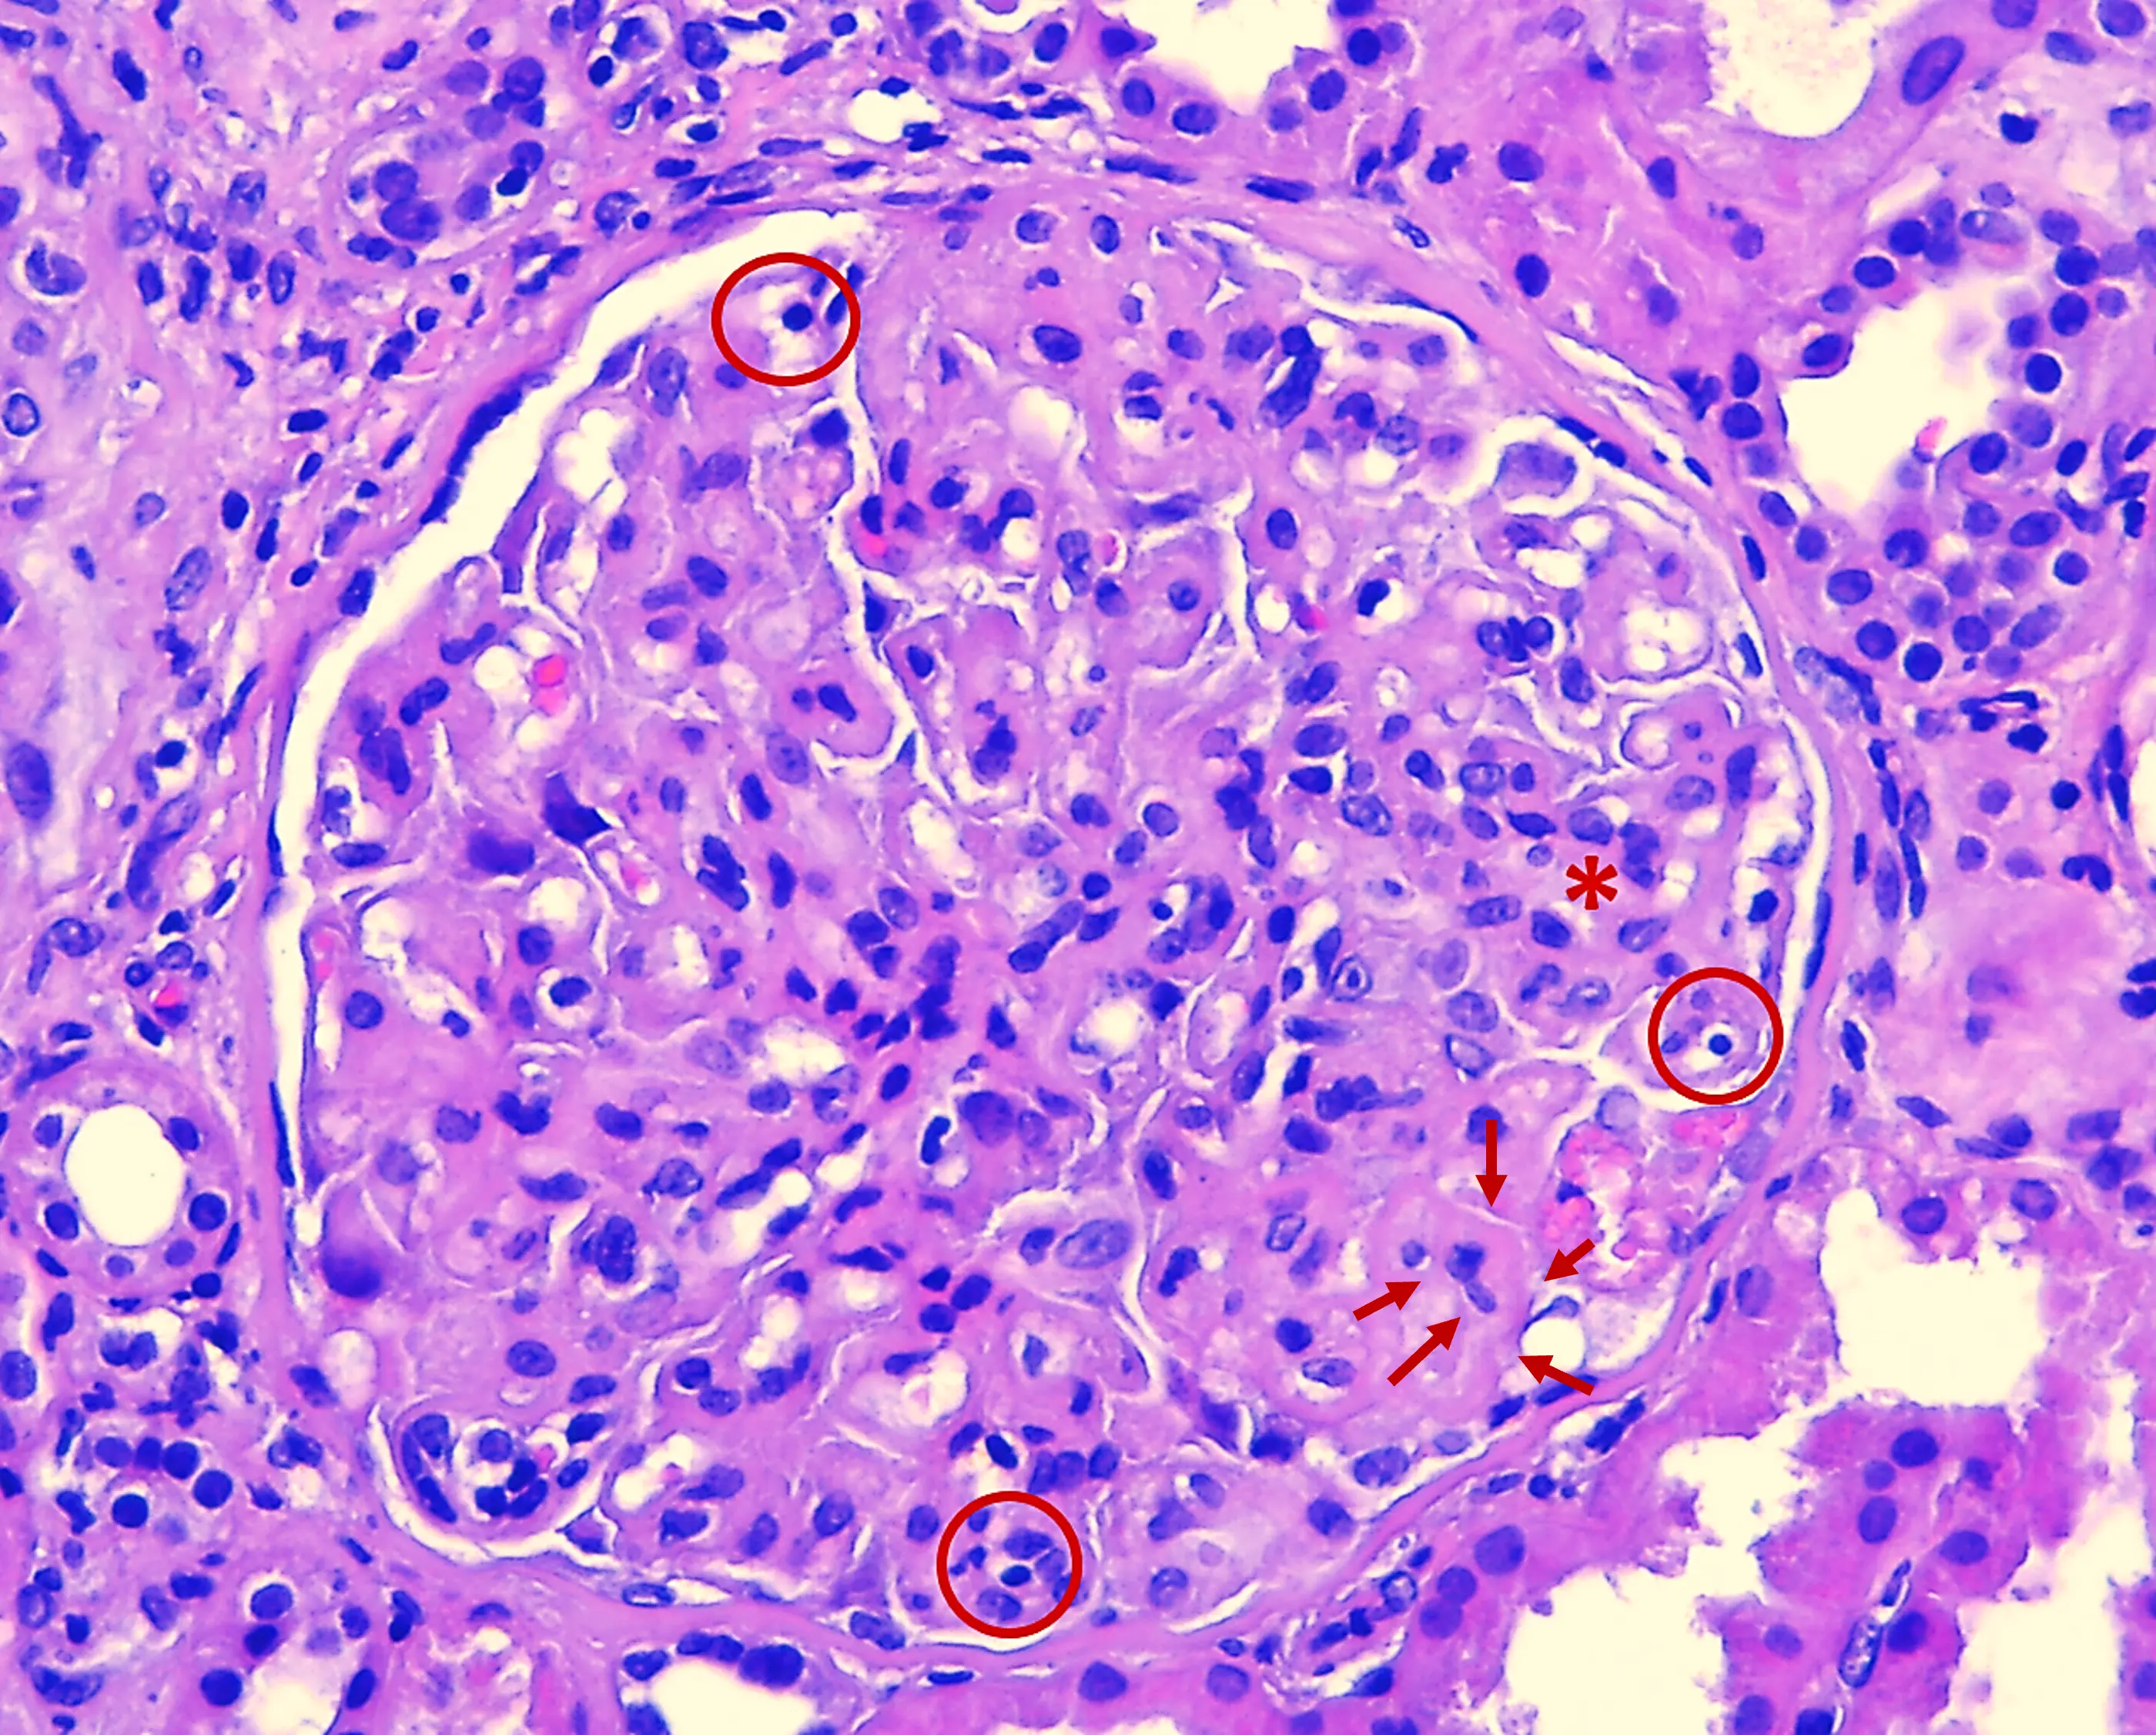

Microscopía óptica H&E con patrón GNMP en Glomerulopatía C3: hipercelularidad endocapilar

Img. 4. H&E. Glomérulo con hipercelularidad endocapilar (O rojo) y proliferación mesangial (* rojo). Se aprecia engrosamiento de las asas capilares (→ rojo). 40x.